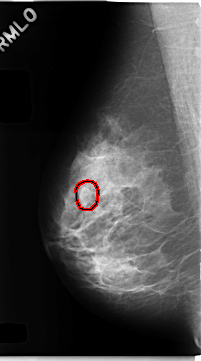

ics_version 1.0 filename C-0234-1 DATE_OF_STUDY 22 12 1994 PATIENT_AGE 40 FILM FILM_TYPE REGULAR DENSITY 2 DATE_DIGITIZED 28 4 1998 DIGITIZER LUMISYS LASER SEQUENCE LEFT_CC LINES 4736 PIXELS_PER_LINE 2240 BITS_PER_PIXEL 12 RESOLUTION 50 NON_OVERLAY LEFT_MLO LINES 4760 PIXELS_PER_LINE 2680 BITS_PER_PIXEL 12 RESOLUTION 50 NON_OVERLAY RIGHT_CC LINES 4760 PIXELS_PER_LINE 2512 BITS_PER_PIXEL 12 RESOLUTION 50 OVERLAY RIGHT_MLO LINES 4688 PIXELS_PER_LINE 2608 BITS_PER_PIXEL 12 RESOLUTION 50 OVERLAY |

FILE: C_0234_1.RIGHT_MLO.OVERLAY TOTAL_ABNORMALITIES 1 ABNORMALITY 1 LESION_TYPE MASS SHAPE OVAL MARGINS MICROLOBULATED ASSESSMENT 4 SUBTLETY 4 PATHOLOGY BENIGN TOTAL_OUTLINES 1 BOUNDARY |